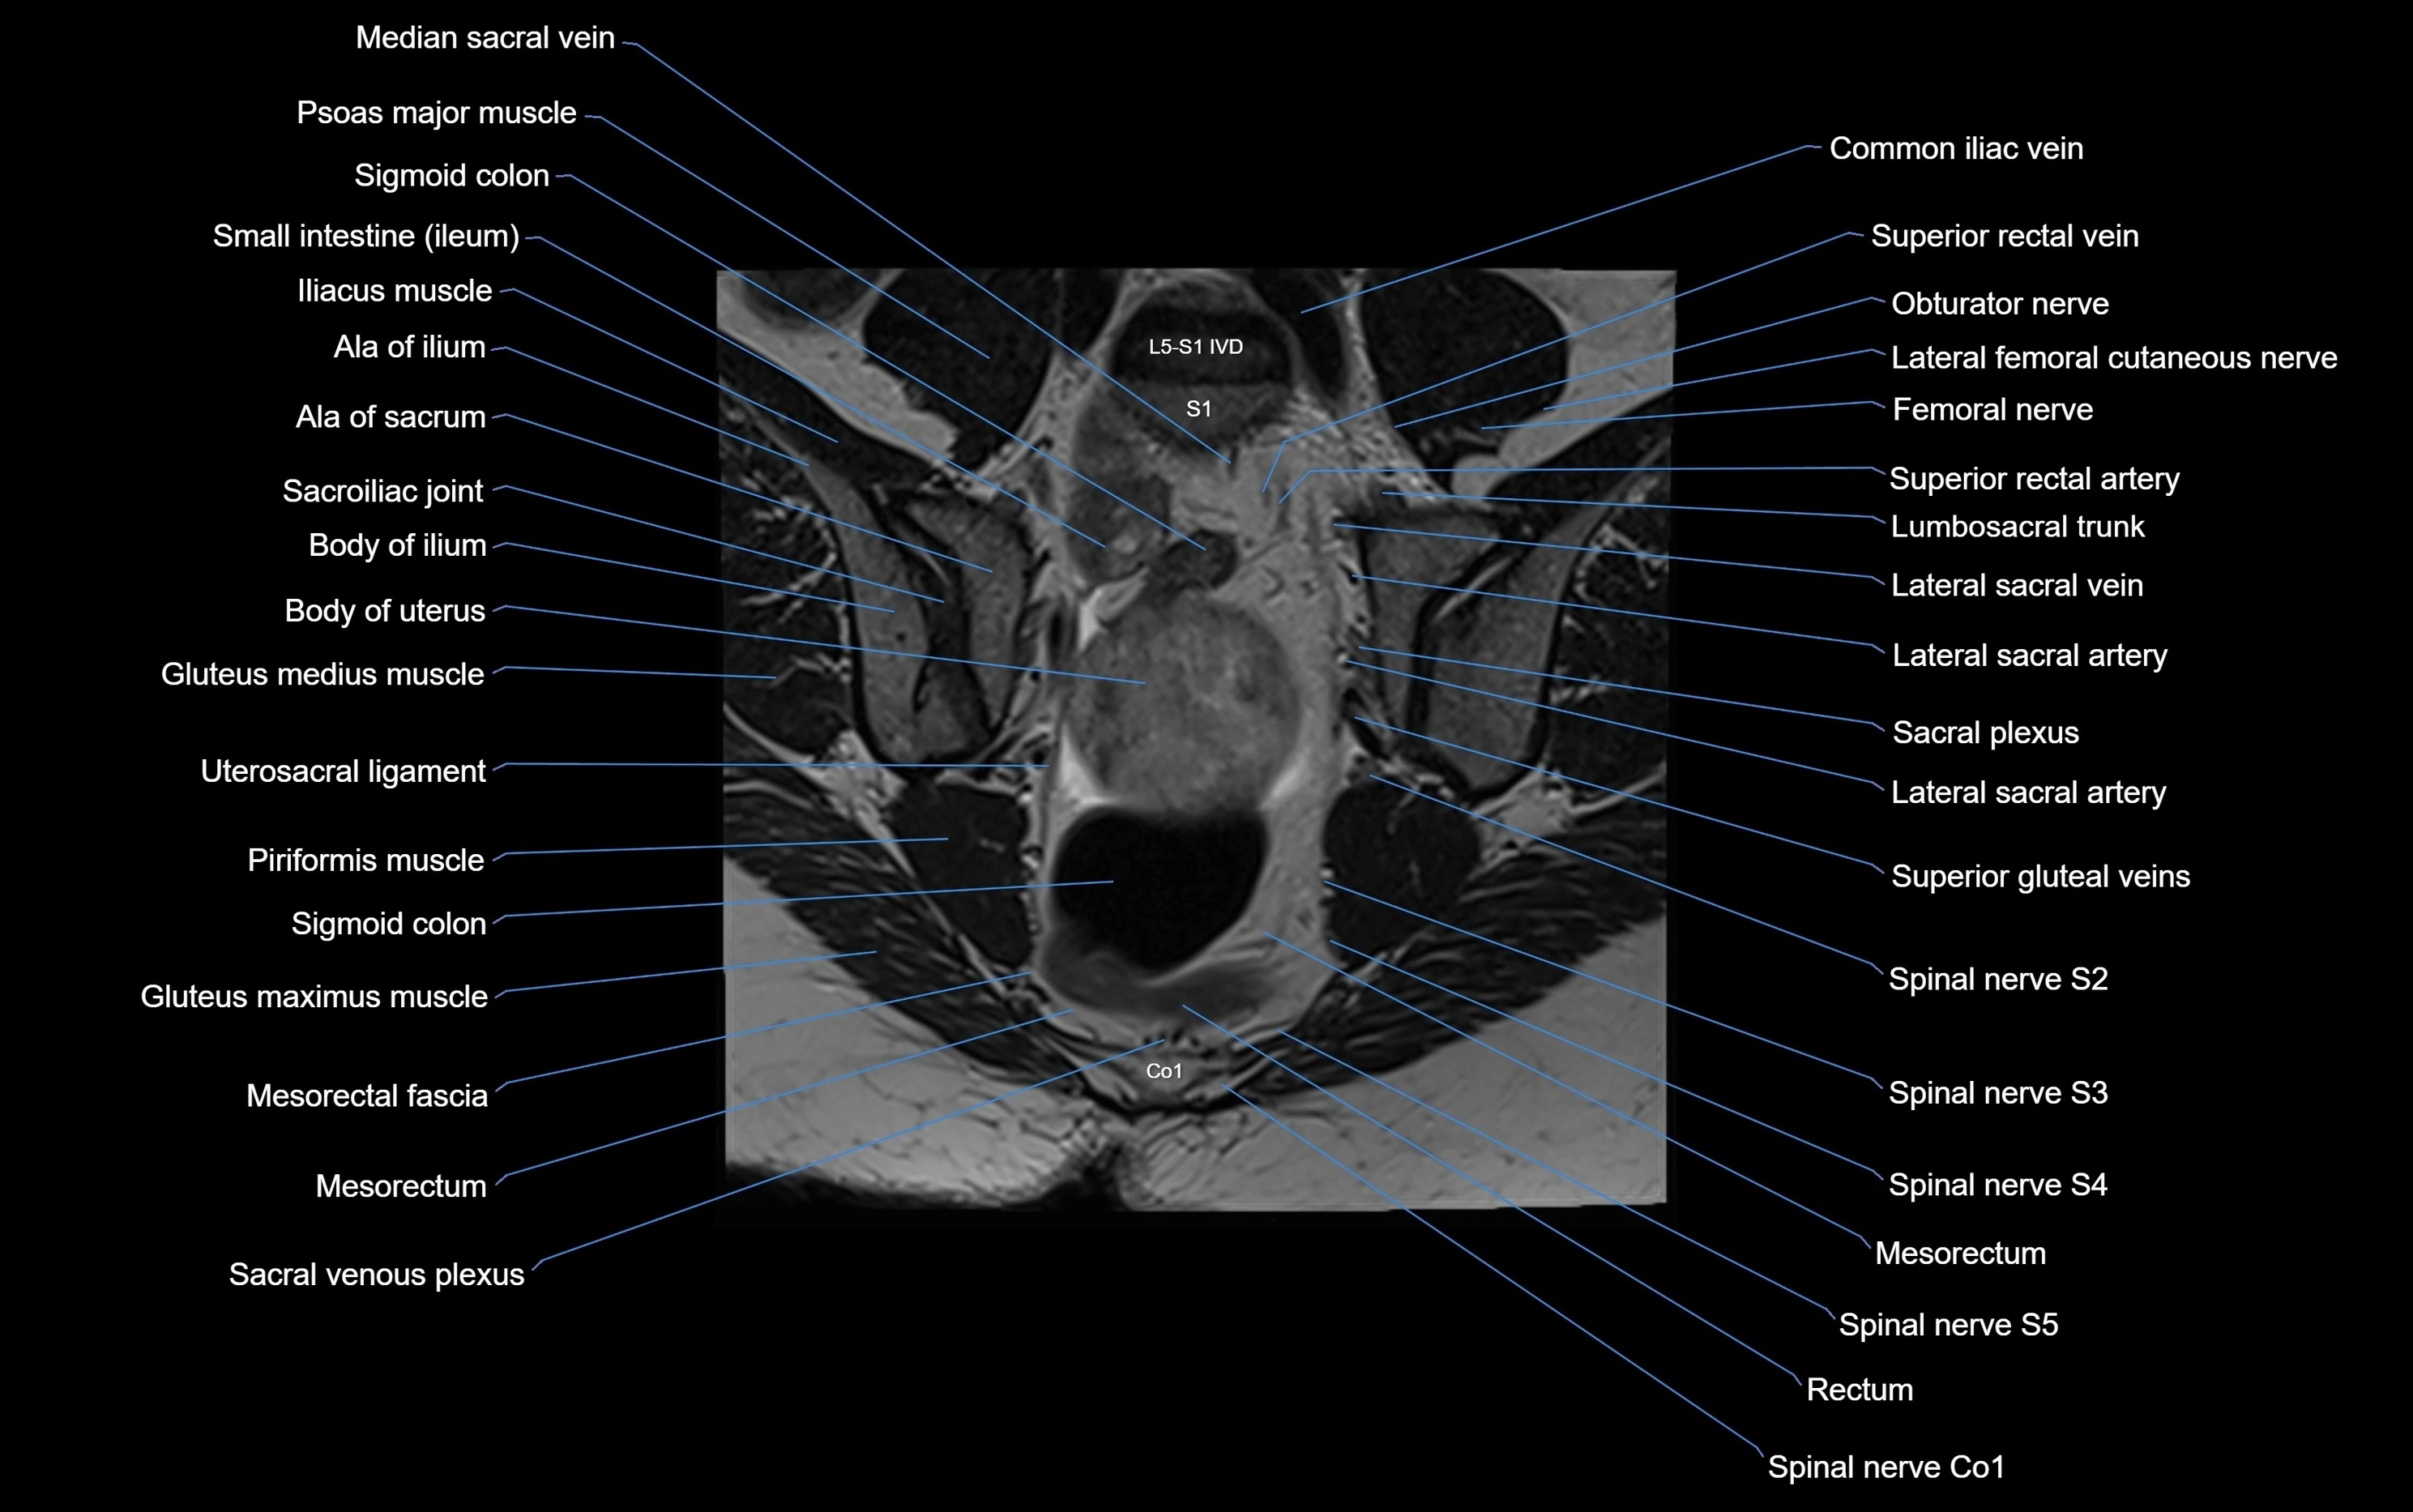

MRI image

image